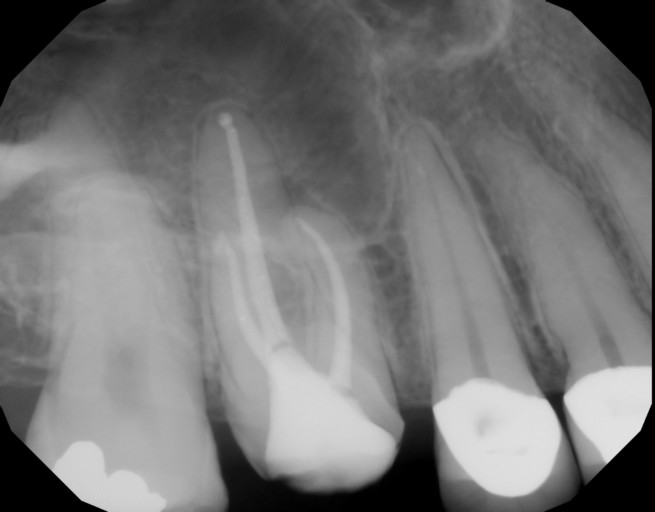

Root canal re-treatment- periapical cyst

Hi, I had a root canal re-treatment due to a periapical cyst. I had no symptoms but decided to be proactive. The doctor opened the canal and drained it. A week later the doctor disinfected the canal and filled it in. He didn't use calcium hydroxide at any time during the treatment. He explained that there was no need for it because the canal looked clean. It's been 7 months but I haven't checked the size of the cyst yet. Was the doctor correct in his decision or was the calcium hydroxide use necessary in my case? Thank you

Hi, I had a root canal re-treatment due to a periapical cyst. I had no symptoms but decided to be proactive. The doctor opened the canal and drained it. A week later the doctor disinfected the canal and filled it in. He didn't use calcium hydroxide...